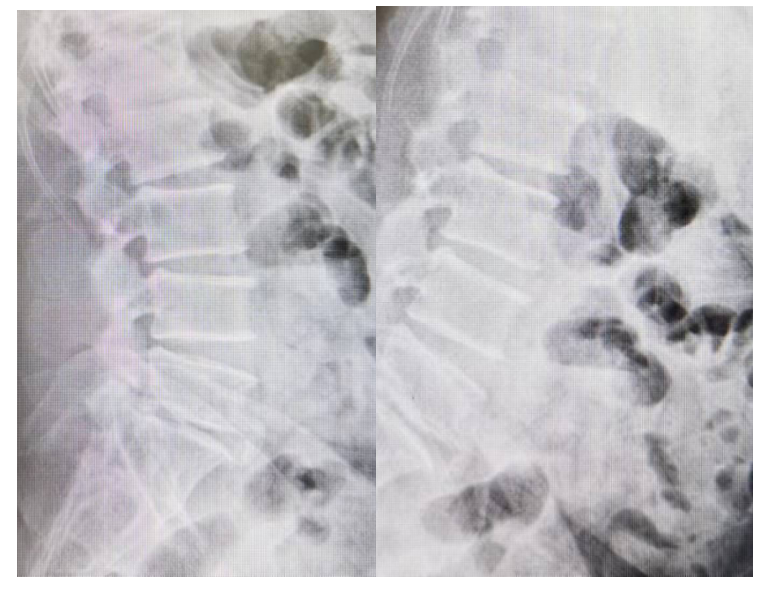

主诉:腰部疼痛3年,加重伴双下肢疼痛麻木1年

现病史:3年前出现腰部疼痛、酸困,无下肢疼痛麻木不适,弯腰活动受限,行走及站立时疼痛加重,平卧休息稍减轻,未治疗,上述症状持续加重,近1年来又出现双下肢疼痛麻木,以左侧为著,步行困难,步行能力约100米,为求诊治,现来我院,遂以“腰椎管狭窄症”为诊断收住我科。发病以来,饮食正常,睡眠一般,体力正常,大小便正常。